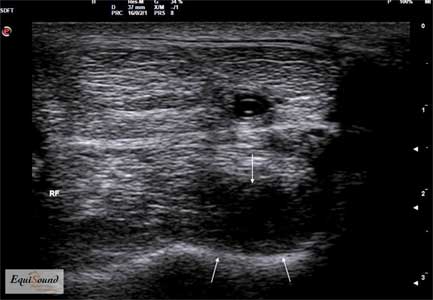

Image échographique en vue longitudinale de l’insertion proximale du suspenseur du boulet chez un cheval présentant une lésion dégénérative au niveau du lobe médial. (La région proximale est à gauche, la région distale à droite)

Image échographique en vue transversale de l’insertion proximale du suspenseur du boulet chez un cheval présentant une lésion dégénérative au niveau du lobe médial. (La région latérale est à gauche, la région médiale à droite)

Image échographique en vue longitudinale de l’insertion distale du tendon d’Achille chez un chien présentant une lésion dégénérative d’évolution chronique. (La région proximale est à gauche, la région distale à droite)